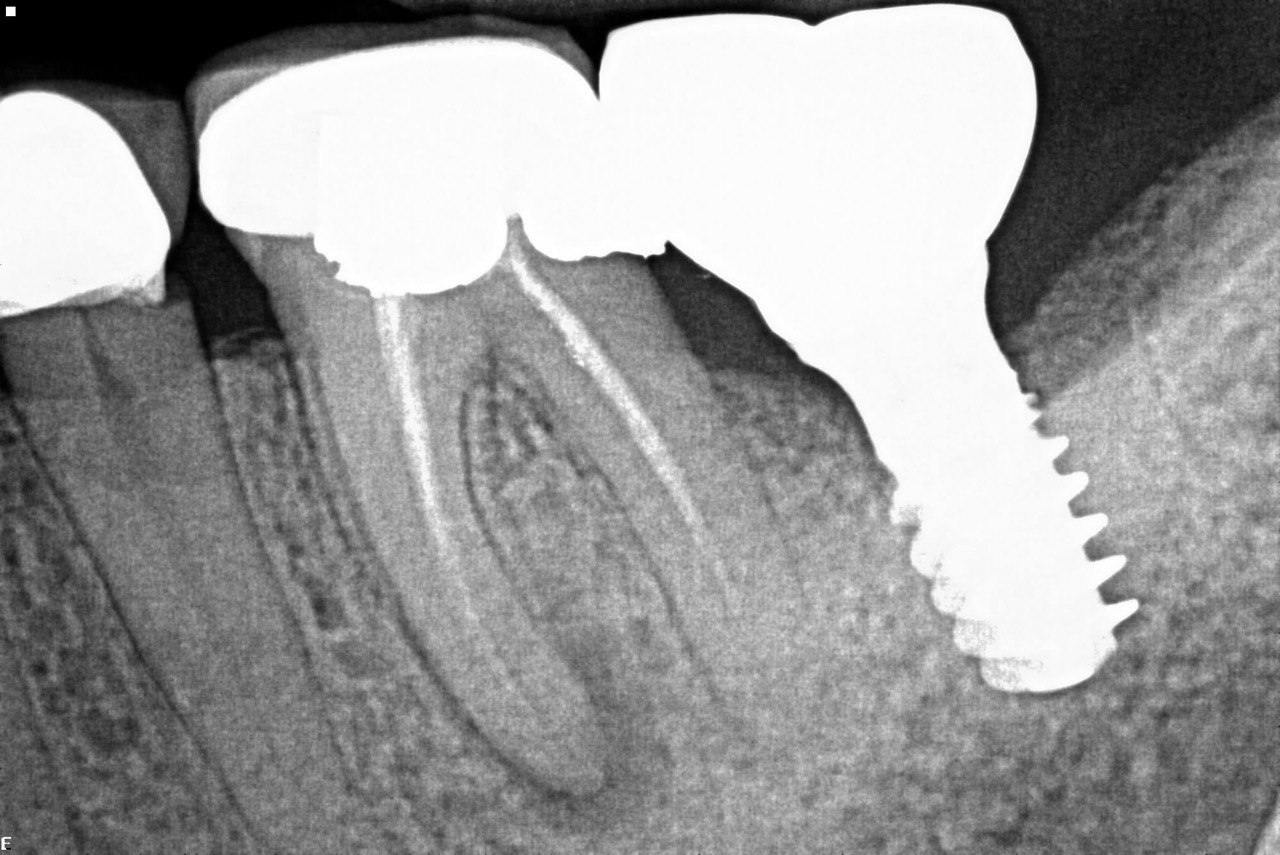

1. What option can be selected regarding the implant seen in this X ray?